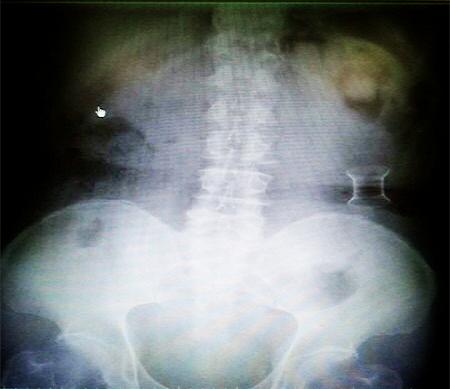

受试患者在结肠端端吻合术中,使用我司新研制产品达到了理想的预期效果。患者术后7天、14天X光片显影,可降解肠道支架均能按研制设计的预期时间节点保持应有强度,术后21天X光片显示可降解肠道支架已完全破碎,并排出体外。在整个试验过程中,病患无任何不良反映,耐受良好。